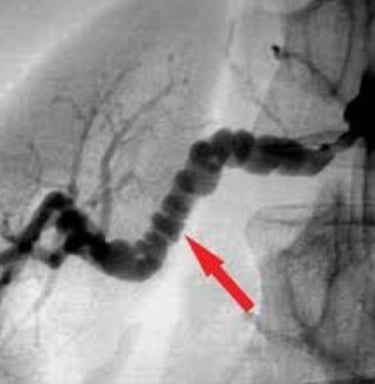

Onu tanımanın yolu, laboratuvar kağıtlarına değil, hastanın bacaklarına (Livedo) ve anjiyografisindeki o ürkütücü "tespih tanelerine" bakmaktır.

En karakteristik özelliği, damar duvarını zayıflatarak oluşturduğu mikro-anevrizmalardır. Anjiyografide bu anevrizmalar bir ip üzerine dizilmiş boncuklar gibi görünür (Rosary Sign).

Anjiyografide Mikroanevrizmalar: LR+ ∞ (sonsuz). Altın Standart. Böbrek veya mezenter (bağırsak) damarlarında tespih tanesi görünümü.